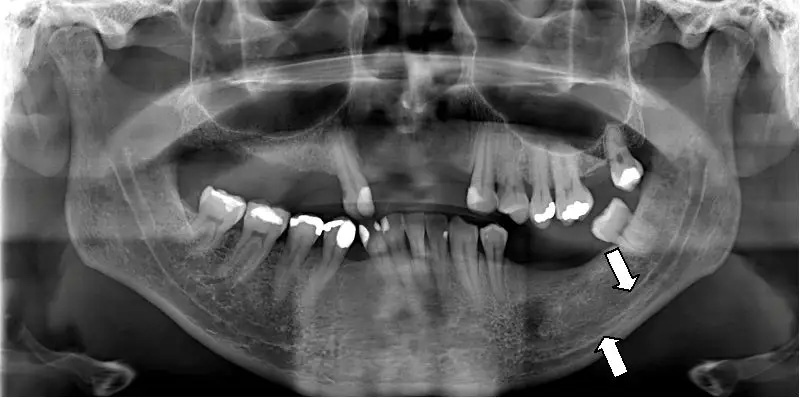

Panoramic X-rays are effective at identifying conditions such as impacted or unerupted teeth, large cysts or tumors, extensive infections, jaw fractures, and gross bone abnormalities. They also reveal the position of wisdom teeth, abnormal jaw growth, and large-scale dental development issues in children and adolescents. These findings can be critical for planning extractions, orthodontic treatment, or oral surgery.

In addition to dental and bony pathologies, panoramic imaging can show sinus changes and some signs of temporomandibular joint involvement, which can guide further evaluation. When a panoramic image suggests a focal lesion or the need for precise bone measurements, the dentist may order more detailed imaging to define the extent and nature of the problem. Overall, the panoramic view is a powerful screening tool for many oral and maxillofacial conditions.

Panoramic images are interpreted by the treating dentist and, when appropriate, by dental specialists or oral and maxillofacial radiologists for complex findings. The clinicians look for anatomical landmarks, pathology, developmental issues, and relationships between teeth and surrounding bone. If the dentist identifies an area that requires more detailed assessment, they may recommend targeted intraoral films or advanced imaging for clarification.

Panoramic imaging has limitations, including lower resolution for small carious lesions, distortion of structures at the image periphery, and superimposition of anatomical features that can obscure detail. Because of these constraints, panoramic films may not show early-stage cavities or fine root fractures as reliably as intraoral films or three-dimensional studies. Clinicians recognize these strengths and limits when selecting the appropriate imaging modality.